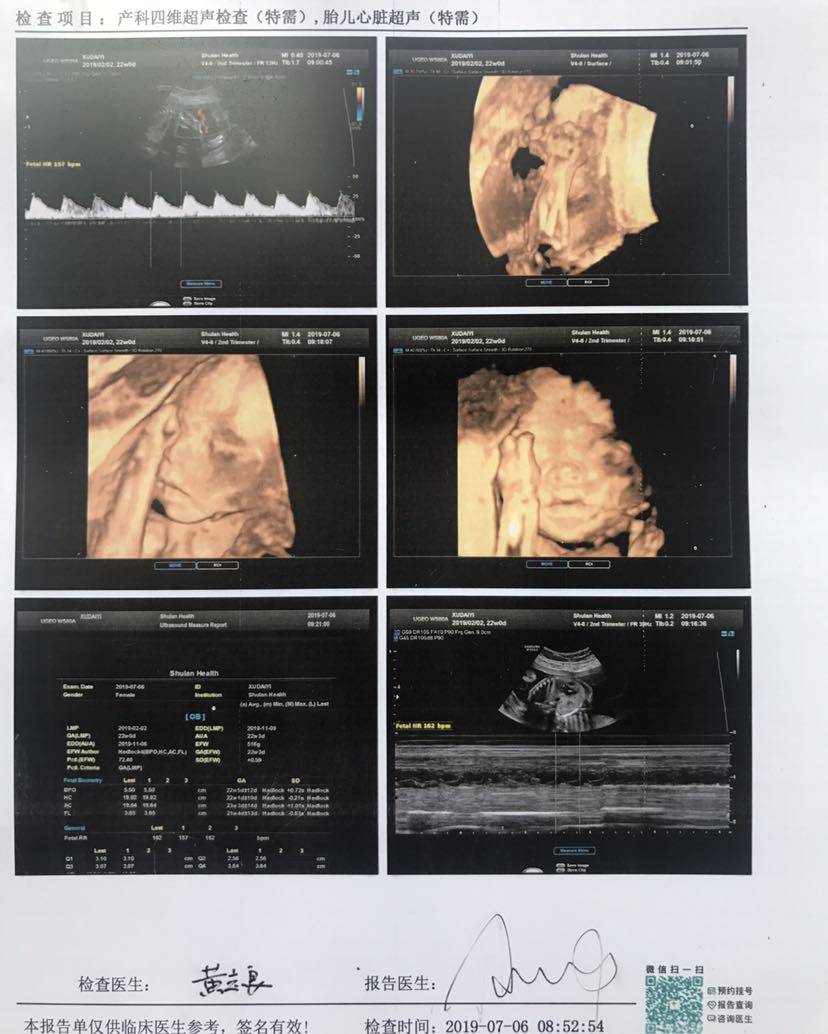

今天四维彩超和胎儿心脏超声顺利通过😁

今天宝宝22周了,12+6做NT的时候就预约了今天的四维和胎心超声,一切正常,悬着的心放下了,因为我抗核抗体ssa阳性、ssb弱阳,所以有点担心,现在可以安心了,做四维的时候医生说,看来你要爬半个小时楼梯了,今天做了三个都要爬,然后让我半侧躺,没想到一下子全部做好了,那心情跟坐过山车一样,出来的时候外面等着的人羡慕我做的快😄还好我宝宝乖,NT一次性过,糖筛也一次性过,四维也一次性过,胎儿心脏超声也一次性过,接下去就等24周以后的糖耐了,估计也会一次性过✌️